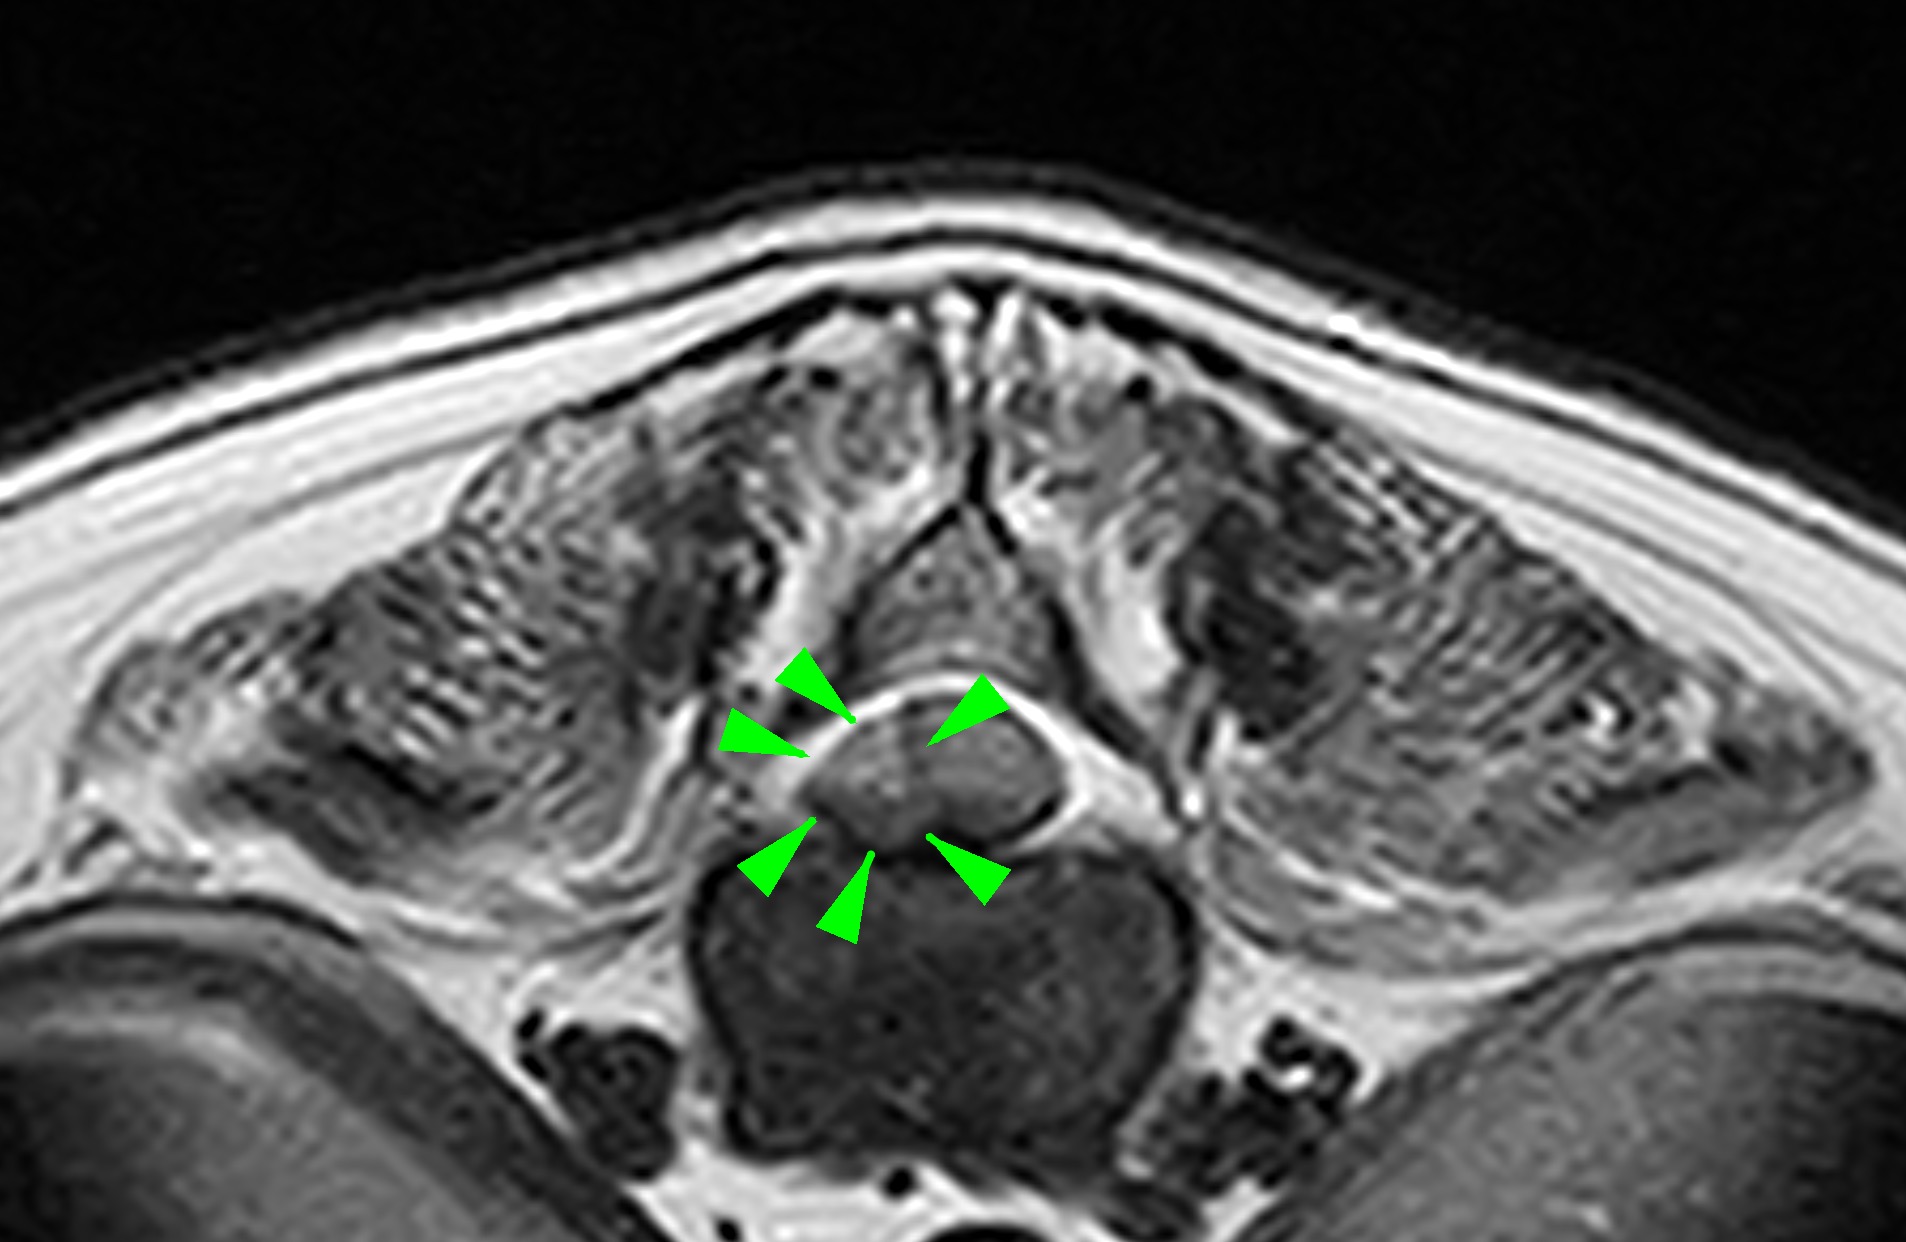

MRI画像(T2-Axial像:この症例では右側からの圧迫が認められました)

MRI画像検査の症例は右側片側椎弓切除術を実施しました。